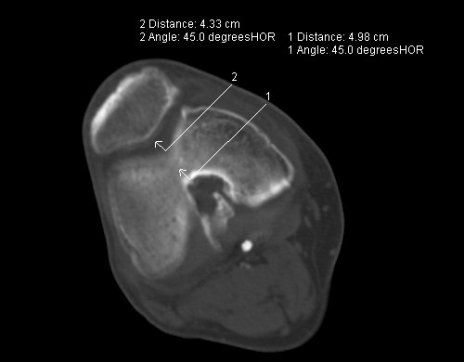

- Insertionstendinopathie der Achillessehne (Achillodynie): chronische Sehnenscheidenentzündung der Achillessehne mit eingeschränkten und schmerzhaften Bewegungen der Ferse oder des Sprunggelenkes möglicherweise entstanden nach Sportverletzungen oder Überbelastung des Sprunggelenkes.